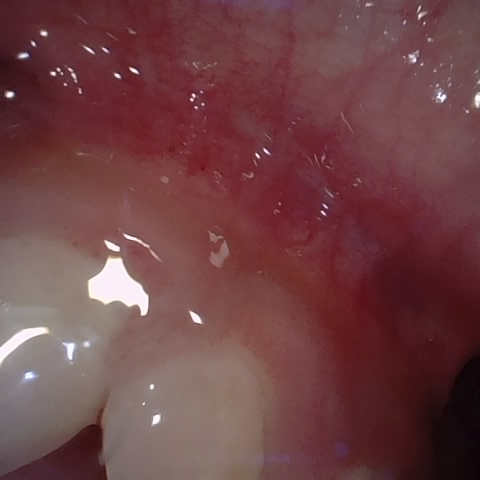

Annotated as "Bad"